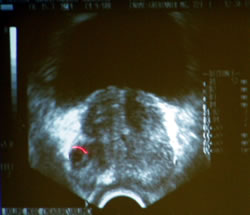

Значение ТРУЗИ при биопсии простаты

- Точное определение

размеров позволяет планировать количество

биопатов

- Визуальный

контроль за позиционированием в соответствии

с зональной анатомией и топографией простаты

контроль за биопсией семенных пузырьков

- Наведение

на подозрительные эхонегативные зоны